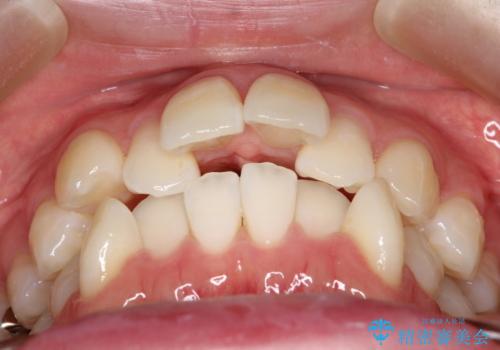

- 出っぱによる口元の閉じにくさを主訴に来院されました。上顎の出っ歯と上下顎叢生も認められたため、上下顎両側4番抜歯を行い、ワイヤー矯正で治療する治療計画を立てました。

上顎にはMI(マイクロインプラント)を埋入して固定源とすることで出っ歯の改善を図りました。

少しスペースクローズに時間がかかりましたが、MIを用いたワイヤー矯正で

主訴である出っ歯と叢生が改善されました。口も閉じやすくなり、スッキリとした口元になりました。